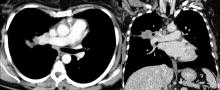

This video shows a 49-year-old woman with a 3.8 cm right upper lobe tumor, surrounding the segmental division of the upper lobe bronchus. The tumor was very close to the pulmonary artery (PA), and had extended contact with the minor fissure (Figure 1 [4]). There were also enlarged lymph nodes posterior to the anterior trunk of the PA surrounding the upper lobe bronchus and posterior to the middle lobe bronchus.